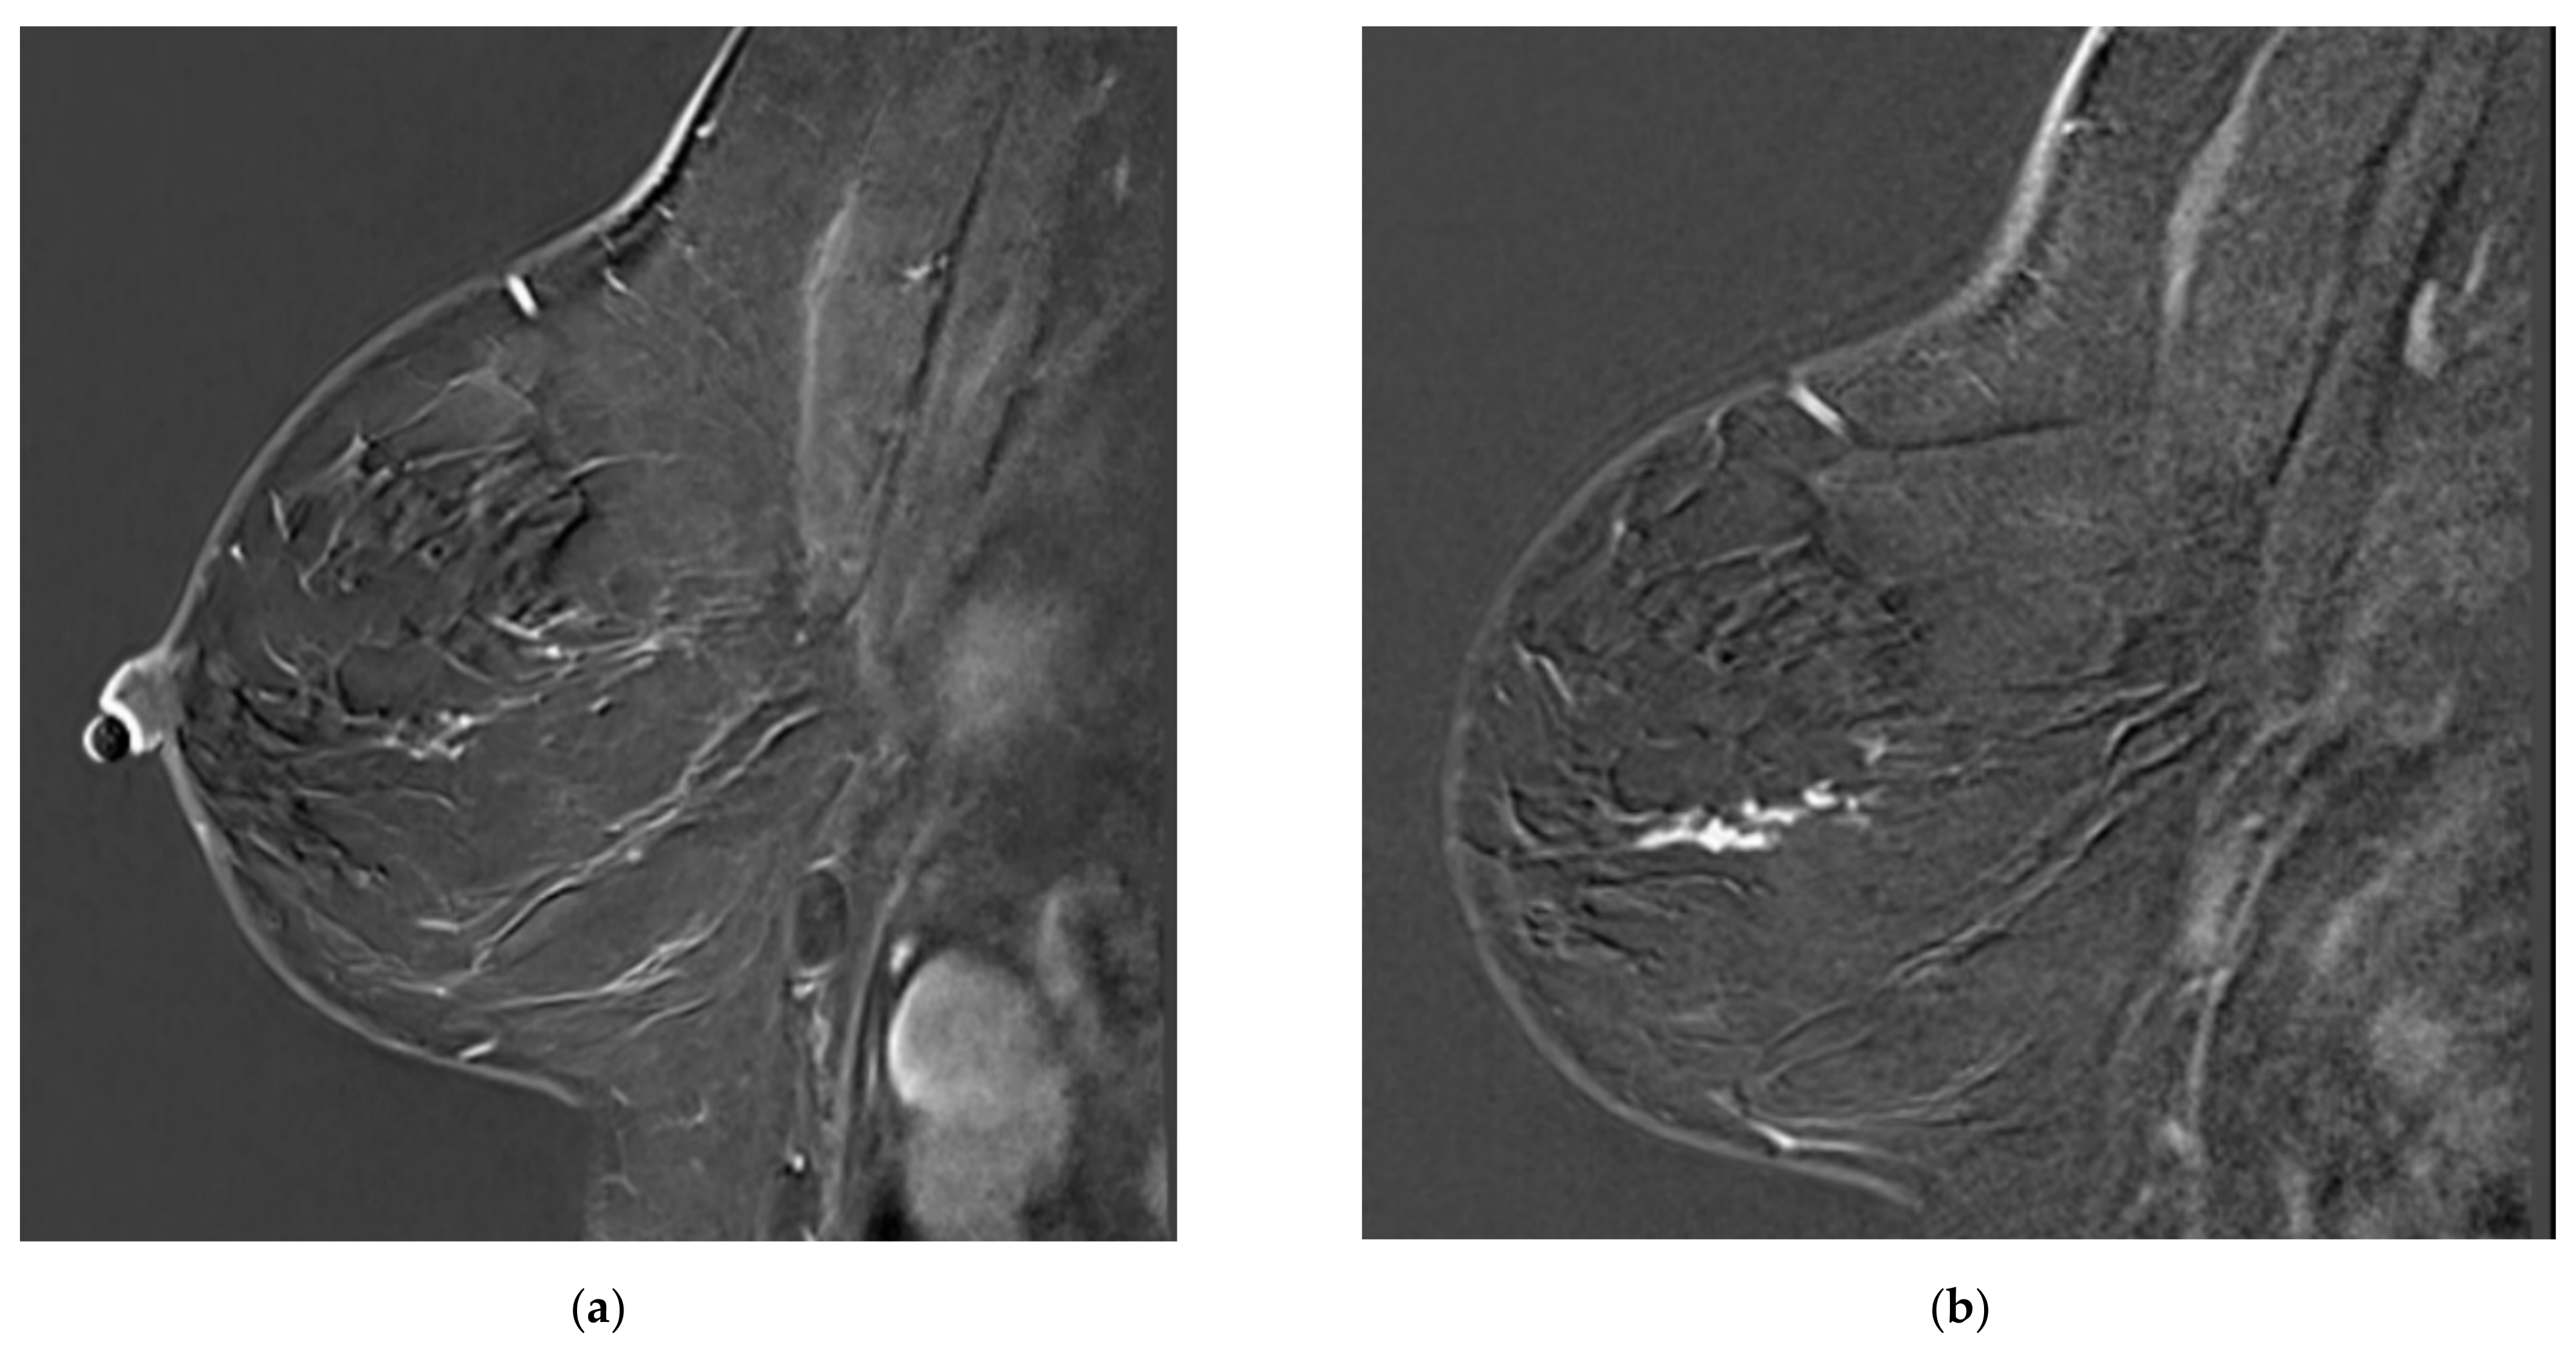

Figure 1.

Examples of missed lesions. Overlooked linear non-mass enhancement: (a) MR A; (b) follow-up MRI (MR B) one year later showing more conspicuous non-mass enhancement, corresponding to DCIS.